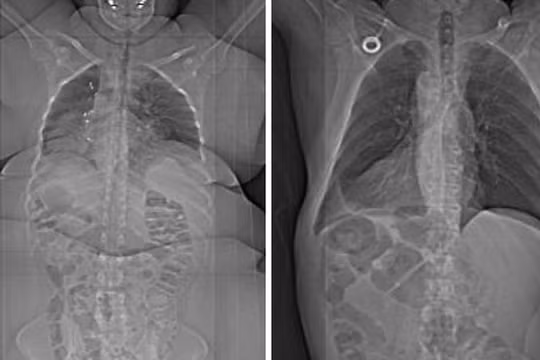

VietTimes -- Có thể bạn chưa biết, cơ thể con người là một hệ thống vô cùng kỳ diệu. Hầu hết mọi người đều tò mò không biết các cơ quan trong cơ thể có cấu tạo và vận hành thế nào? 15 bức ảnh sau đây sẽ giúp bạn giải đáp những thắc mắc đó.